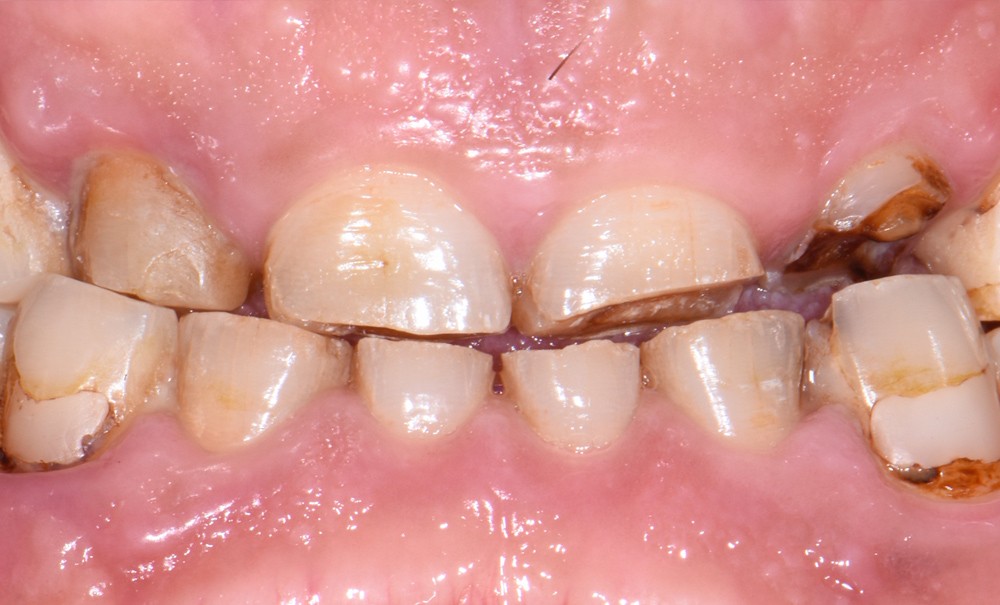

Au vu du contexte para-fonctionnel et de l’étendue de la perte tissulaire, des coiffes périphériques minimalement invasives ont été choisies afin de restaurer l’esthétique et la fonction. Actuellement, aucun consensus n’est fait sur le choix du matériau d’infrastructure à privilégier. Les matériaux hybrides usinables présentent des propriétés mécaniques, physiques et biologiques intéressantes en contexte d’usure sévère (e.g., module d’élasticité, résistance à la propagation de fêlures, facilité de réintervention). Une réhabilitation globale avec remontée de dimension verticale d’occlusion (DVO) par l’intermédiaire de coiffes composites renforcés en nano-céramiques est décrite.